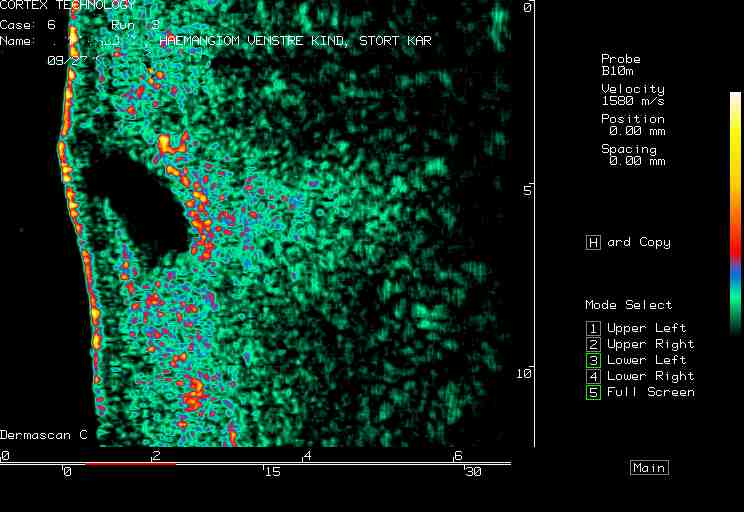

| Vascular lesions |  Port wind stain |

Hemangioma, nose |

Facial hemangioma 1 |

Facial hemangioma 2 |